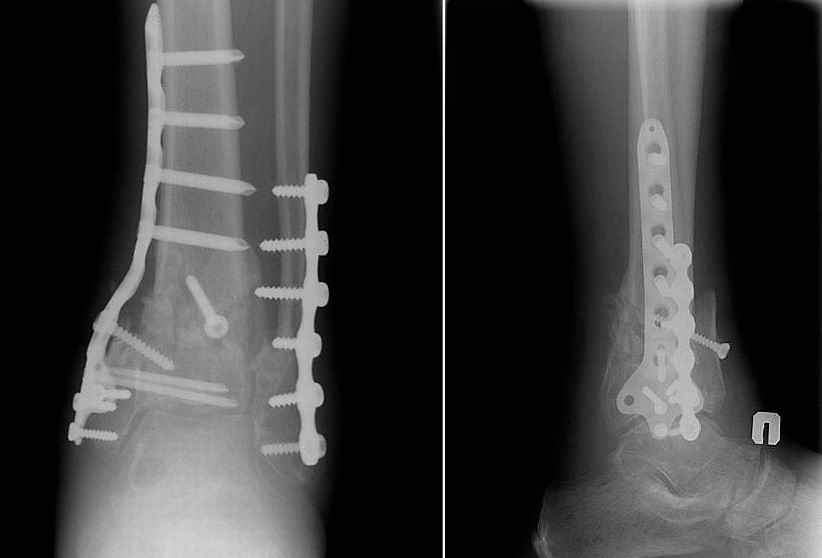

[Ortho] Перелом пилона 6 мес. давности

Прооперировали 6 февраля.

На операции - несращение проксимального диафизарного отломка и осколков эпифиза, которые представляли собой неправильно сросшийся, крепкий конгломерат. С учетом сохранности движений в голеностопном суставе (боясь ему навредить), решено было не разбирать их, а только исправить ось голени, что и было сделано, после остеотомии и резекции малоберцовой кости + остеопластика.

Получилось видимо не идеально, внушает оптимизм хорошее состояние мягких тканей и сохранность движений в голеностопном суставе после операции. Хотя... :)